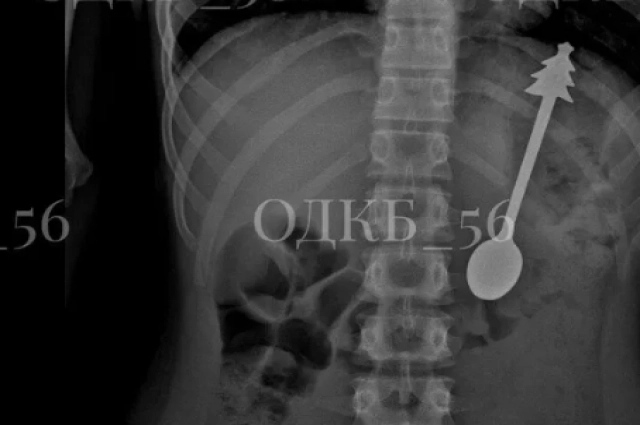

В Оренбургской области в феврале 2026 года врачи экстренно извлекли из желудка ребёнка металлическую ложку длиной 14 сантиметров. На ручке столового прибора была фигурка ёлки.

Врачам удалось извлечь предмет через рот с помощью эндоскопического оборудования, избежав полостной операции. Это значительно сократило восстановительный период и снизило риски для маленького пациента.